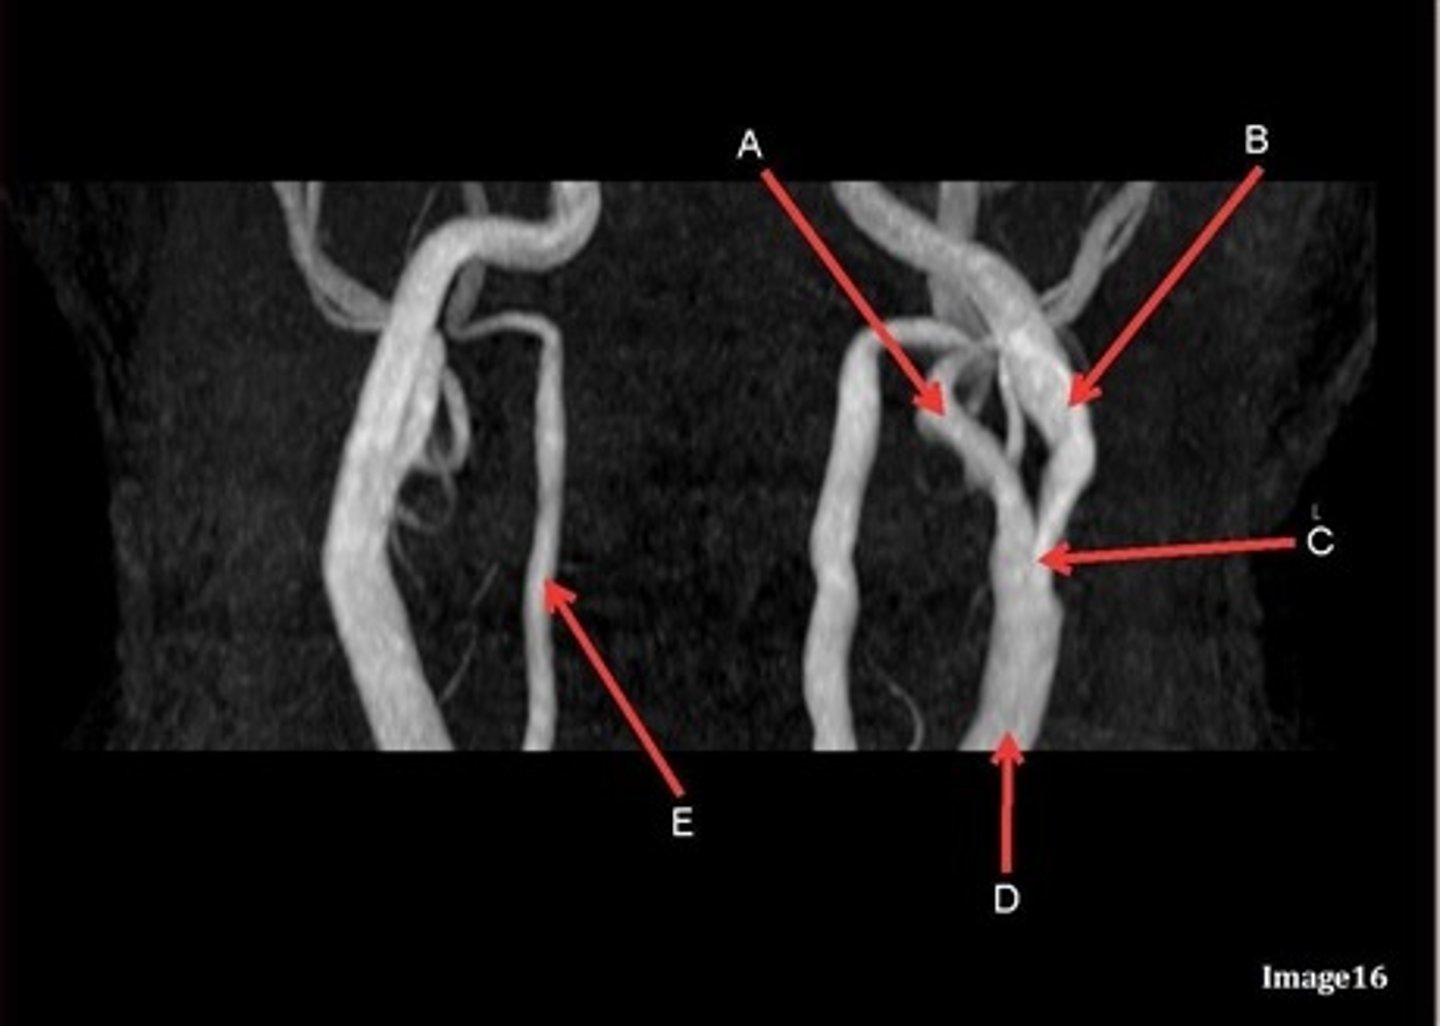

B

posterior frontal vein

C

parietal veins

D

superior sagittal sinus

E

Torcular herophili

F

internal jugular vein

G

R transverse sinus

H

J

R parietal veins

L

L parietal veins

K

Vein of trolard (superior anastomotic vein)

M

Left sigmoid sinus

N

O

P

Left transverse sinus

S

Internal cerebral vein

A

anterior frontal vein

right transverse sinus

left parietal veins

Vein of Trolard